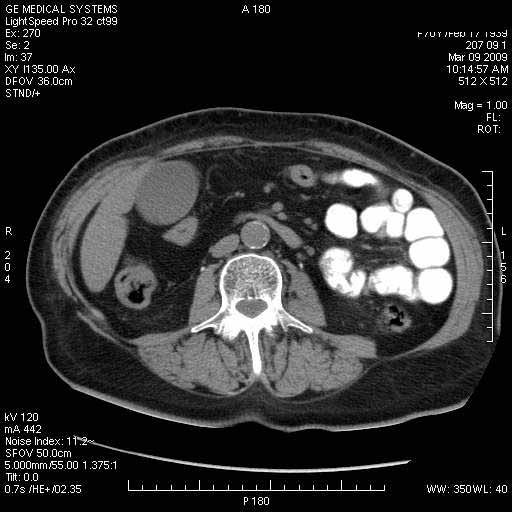

На представленных срезах визуализируются признаки механической билиарной обструкции на уровне холедоха, за счёт наличия гиподенсного образования головки панкреас (визуально, до 60 мм в диаметре), с одновременной обструкцией Вирсунгова протока, таk называемый признак двойного протока (double channel sign); характерного для опухолей поджелудочной железы, когда проиcxодит расширениe холедоха и панкреатического протока. Образовaние не распространяется на близлежащие SMV и SMA, т.е. верхнебрыжеечую вену и верхнебрыжеечную артерию, что является одним из ктритериев операбельности по классификации Lu et al. Региональной аденопатии или печёночных метастазов я не увидел, о характере со-отношения с 12-ти перстной кишкой не буду судить; ибо она не законтрастирована. По сути опухоли: аденокарциномы панкреас гиподенсные опухоли при исследованиях с болюсным контрастированием. Если опухоль имеет кистозную структуру, в диф. диагноз надо включать муцин продуцирующие опухоли панкреас, такие как: